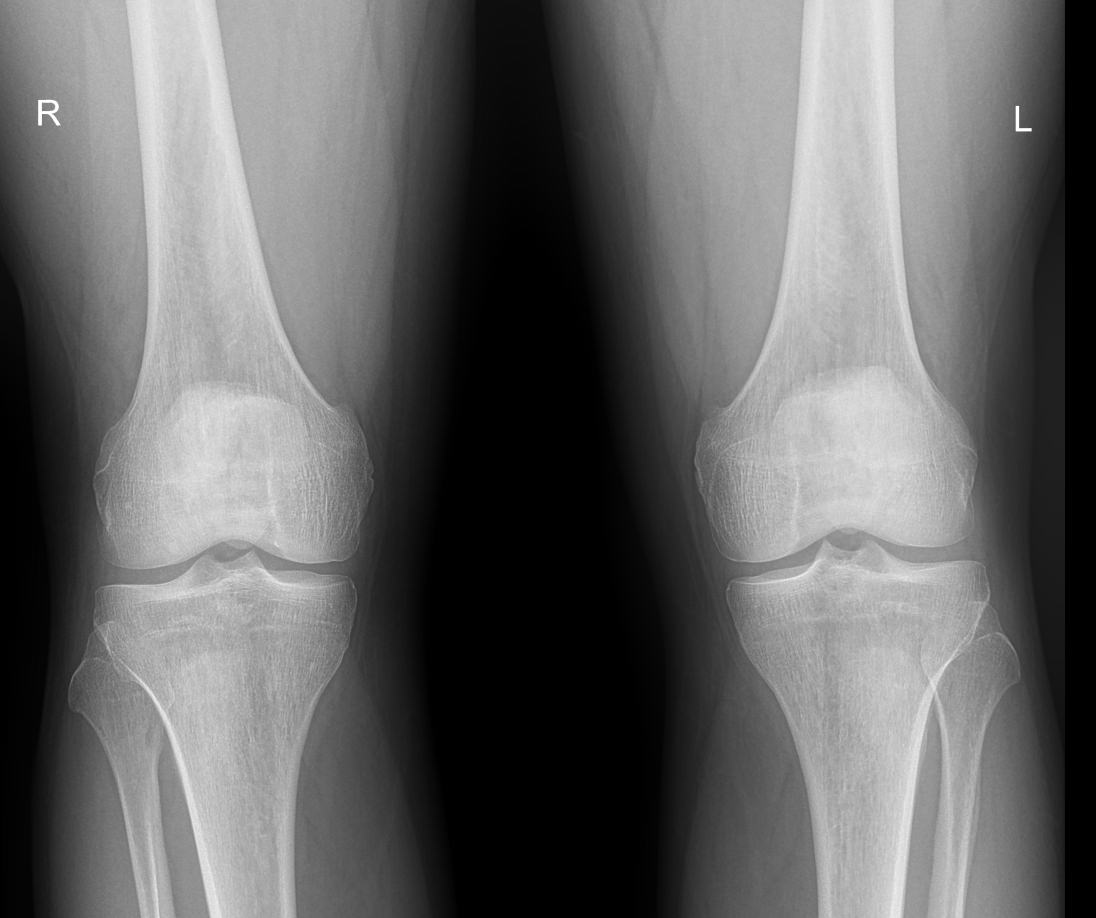

Что покажет рентген обоих коленных суставов в одной проекции

В протоколе у каждого сустава описывается:

• Состояние мягких тканей;

• Суставная щель ― в норме, расширена, сужена, затемнена, имеет дополнительные включения;

• Состояние суставных  поверхностей и их соответствие друг другу ― несоответствие говорит о вывихе;

• Положение надколенника ― обычное или нет;

• Состояние костной ткани и надкостницы ― могут быть обнаружены участки разрежения, размягчения или других патологических процессов, а также свежие и сросшиеся переломы.